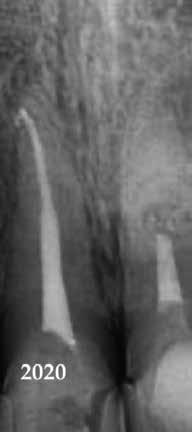

Krell és Caplan kutatásában 2086 repedt fogat vizsgáltak meg. A vizsgált fogak között leggyakrabban a második alsó nagyőrlőfogak (36%), majd ezt követően az első alsó nagyőrlők (27%), és végül az első felső nagyőrlők (18%) fordultak elő. A kutatási eredményeik szerint a fogbél állapota nem befolyásolta jelentős mértékben a kezelés várható kimenetelét. (Irreverzibilis pulpitis 85%; necrosis 80%; korábban gyökérkezelt 74%). A kimenetel szempontjából ugyanígy indifferens volt a páciensek neme, életkora, a kezelés időpontja, a fog pozíciója, a fog helyreállítása során használt anyag típusa, valamint az érintett fogfelszínek száma. 2014 júliusában egy 45 éves hölgy páciens azzal a panasszal kereste fel a rendelőnket, hogy nagyjából 10 napja egy fájdalmas duzzanat alakult ki a jobb felső első kisőrlője koronája mellett (14). A klinikai vizsgálat során egy amalgámtömést találtunk a panaszos fogban. A tömés széli zárása nem volt megfelelő, a disztális záróléc és a tömés között rést tapasztaltunk. A fog disztobukkális és linguális felszíne mellett 8 mm-es csontos tasakokat mértünk. A periapikális felvételen az 14-es foggyökér disztális felszínének megfelelően vertikális irányú radiolucens felritkulást észleltünk. A klinikai vizsgálat során a mesiális zárólécet kettéválasztó törésvonalat detektáltunk (17–18. ábra). A fogszenzibilitás vizsgálata során negatív eredményt kaptunk. A páciensnek ismertettük az elérhető terápiás lehetőségeket: 1, a 14-es fog eltávolítása, majd a foghiány 3 tagú cementezett híddal történő pótlása; 2, a 14-es fog eltávolítása, kemény- és lágyszöveti augmentáció, majd implantátum behelyezése; 3, a 14-es fog gyökérkezelése, gyökértömése és ezt követően a csücsökborítást biztosító restaurátum készítése. Arra is felhívtuk a páciens figyelmét, hogy a 3. terápiás lehetőség választása esetén nem tudjuk a fogmegtartás sikerességét garantálni, de végül – főként anyagi okok miatt – mégis ezt a terápiás opciót választotta. Fontos megjegyezni, hogy a repedt fogak ellátási lehetőségeit a törésvonal mélysége, elhelyezkedése, lefutása nagyban befolyásolja. A kezelés megtervezése során a fog és a fogat körülvevő szövetek állapotával kapcsolatos számtalan különböző faktort kell egyidejűleg figyelembe vennünk. A gyökérkezelést követően a gyökértömést meleg vertikális kondenzációs technikai alkalmazásával készítettük el (19. ábra). A hozzáférési nyílást folyékony és hibrid kompozit tömőanyag segítségével zártuk. A zárás elkészítése során a dr. David Clark által kifejlesztett Bioclear matricarendszert alkalmaztuk. A 6 éves kontroll során készített (2020) röntgenfelvételen a csontos defektus telődése volt megfigyelhető. Ez is a parodontális defektus gyógyulását igazolta (20–21. ábra).

17. ábra: A 14-es fog gyökerének disztális felszíne mellett vertikális csontpusztulásra utaló jelek észlelhetőek. Klinikailag ezen a területen 8 mm mélységű tasakmélységet mértünk. – 18. ábra: A 14-es fog disztális zárólécének megfelelően törésvonal észlelhető, ugyanakkor a csücskök teljes szeparálódására utaló jelek nem láthatóak. Az amalgámtömés eltávolítását követően jól megfigyelhető volt a törésvonal teljes lefutása. – 19. ábra: A gyökértömés elkészítése során meleg vertikális kondenzációs technikát alkalmaztunk. A felvételeken oldalcsatornák jelenlétére utaló jelek is észlelhetőek. – 20–21. ábra: A 2020-ban készült kontrollfelvételeken jól látható a csontos defektus telődése. A radiológiai jelek alapján (jól lekövethető gyökérhártyarés) a parodontális ligamentumok regenerációját is vélelmezzük.